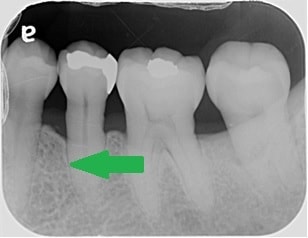

初診時のレントゲンで、赤の矢印が示す黒いところは、簡単に言うと歯周病で歯の周りの骨が溶けてしまっている状態です。

歯周組織再生療法という歯の周りの骨の再生を促す手術後2年6ヶ月後のレントゲンでは、緑の矢印で示すように、黒かったところが白く変わっていることが分かるかと思います。溶けてしまっていた骨の再生が、促されていることが推測されます。

このような治療効果も、患者さんご自身でのブラッシングの状態が悪いと長持ちしません。